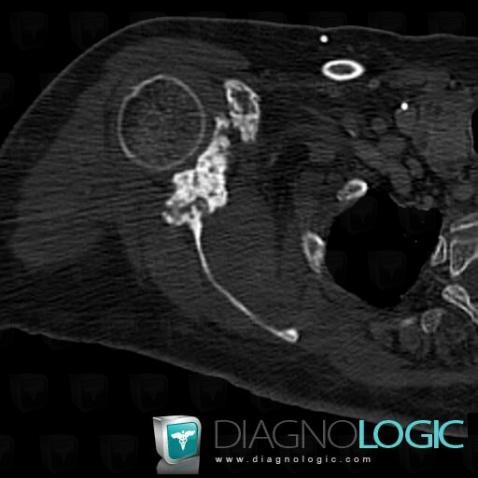

Metastasis, Scapula, CT

Here is the specific information in the key image above:

- Diagnosis Metastasis, Location(s) Scapula, with gamuts Solitary osteosclerotic bone lesion

- Diagnosis Metastasis, Location(s) Scapula, with gamuts Epiphyseal osteolysis, Ill-defined osteolysis